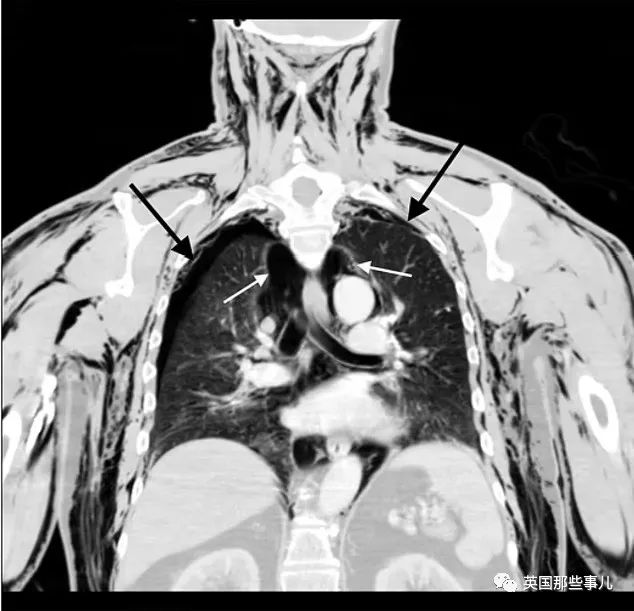

听完老人的介绍后,医生决定先解决老人呼吸困难的问题,于是带他做了CT扫描。

扫描结果显示,老人的肺部塌陷,空气正在他的身体里积聚,这是一种非常危险的情况,很可能危及生命。

上图就是老爷子的CT片子。

其中黑色箭头指向老人塌陷的肺部,白色箭头指的是被困在肺部和胸壁之间的气泡(实心黑色区域)。

老人的颈部、肩部和手臂上都有黑色部分,说明这些部位都积聚着空气。

如果不及时治疗的话,这些空气可能会影响到老人的心脏和肺部的功能,带来生命危险。